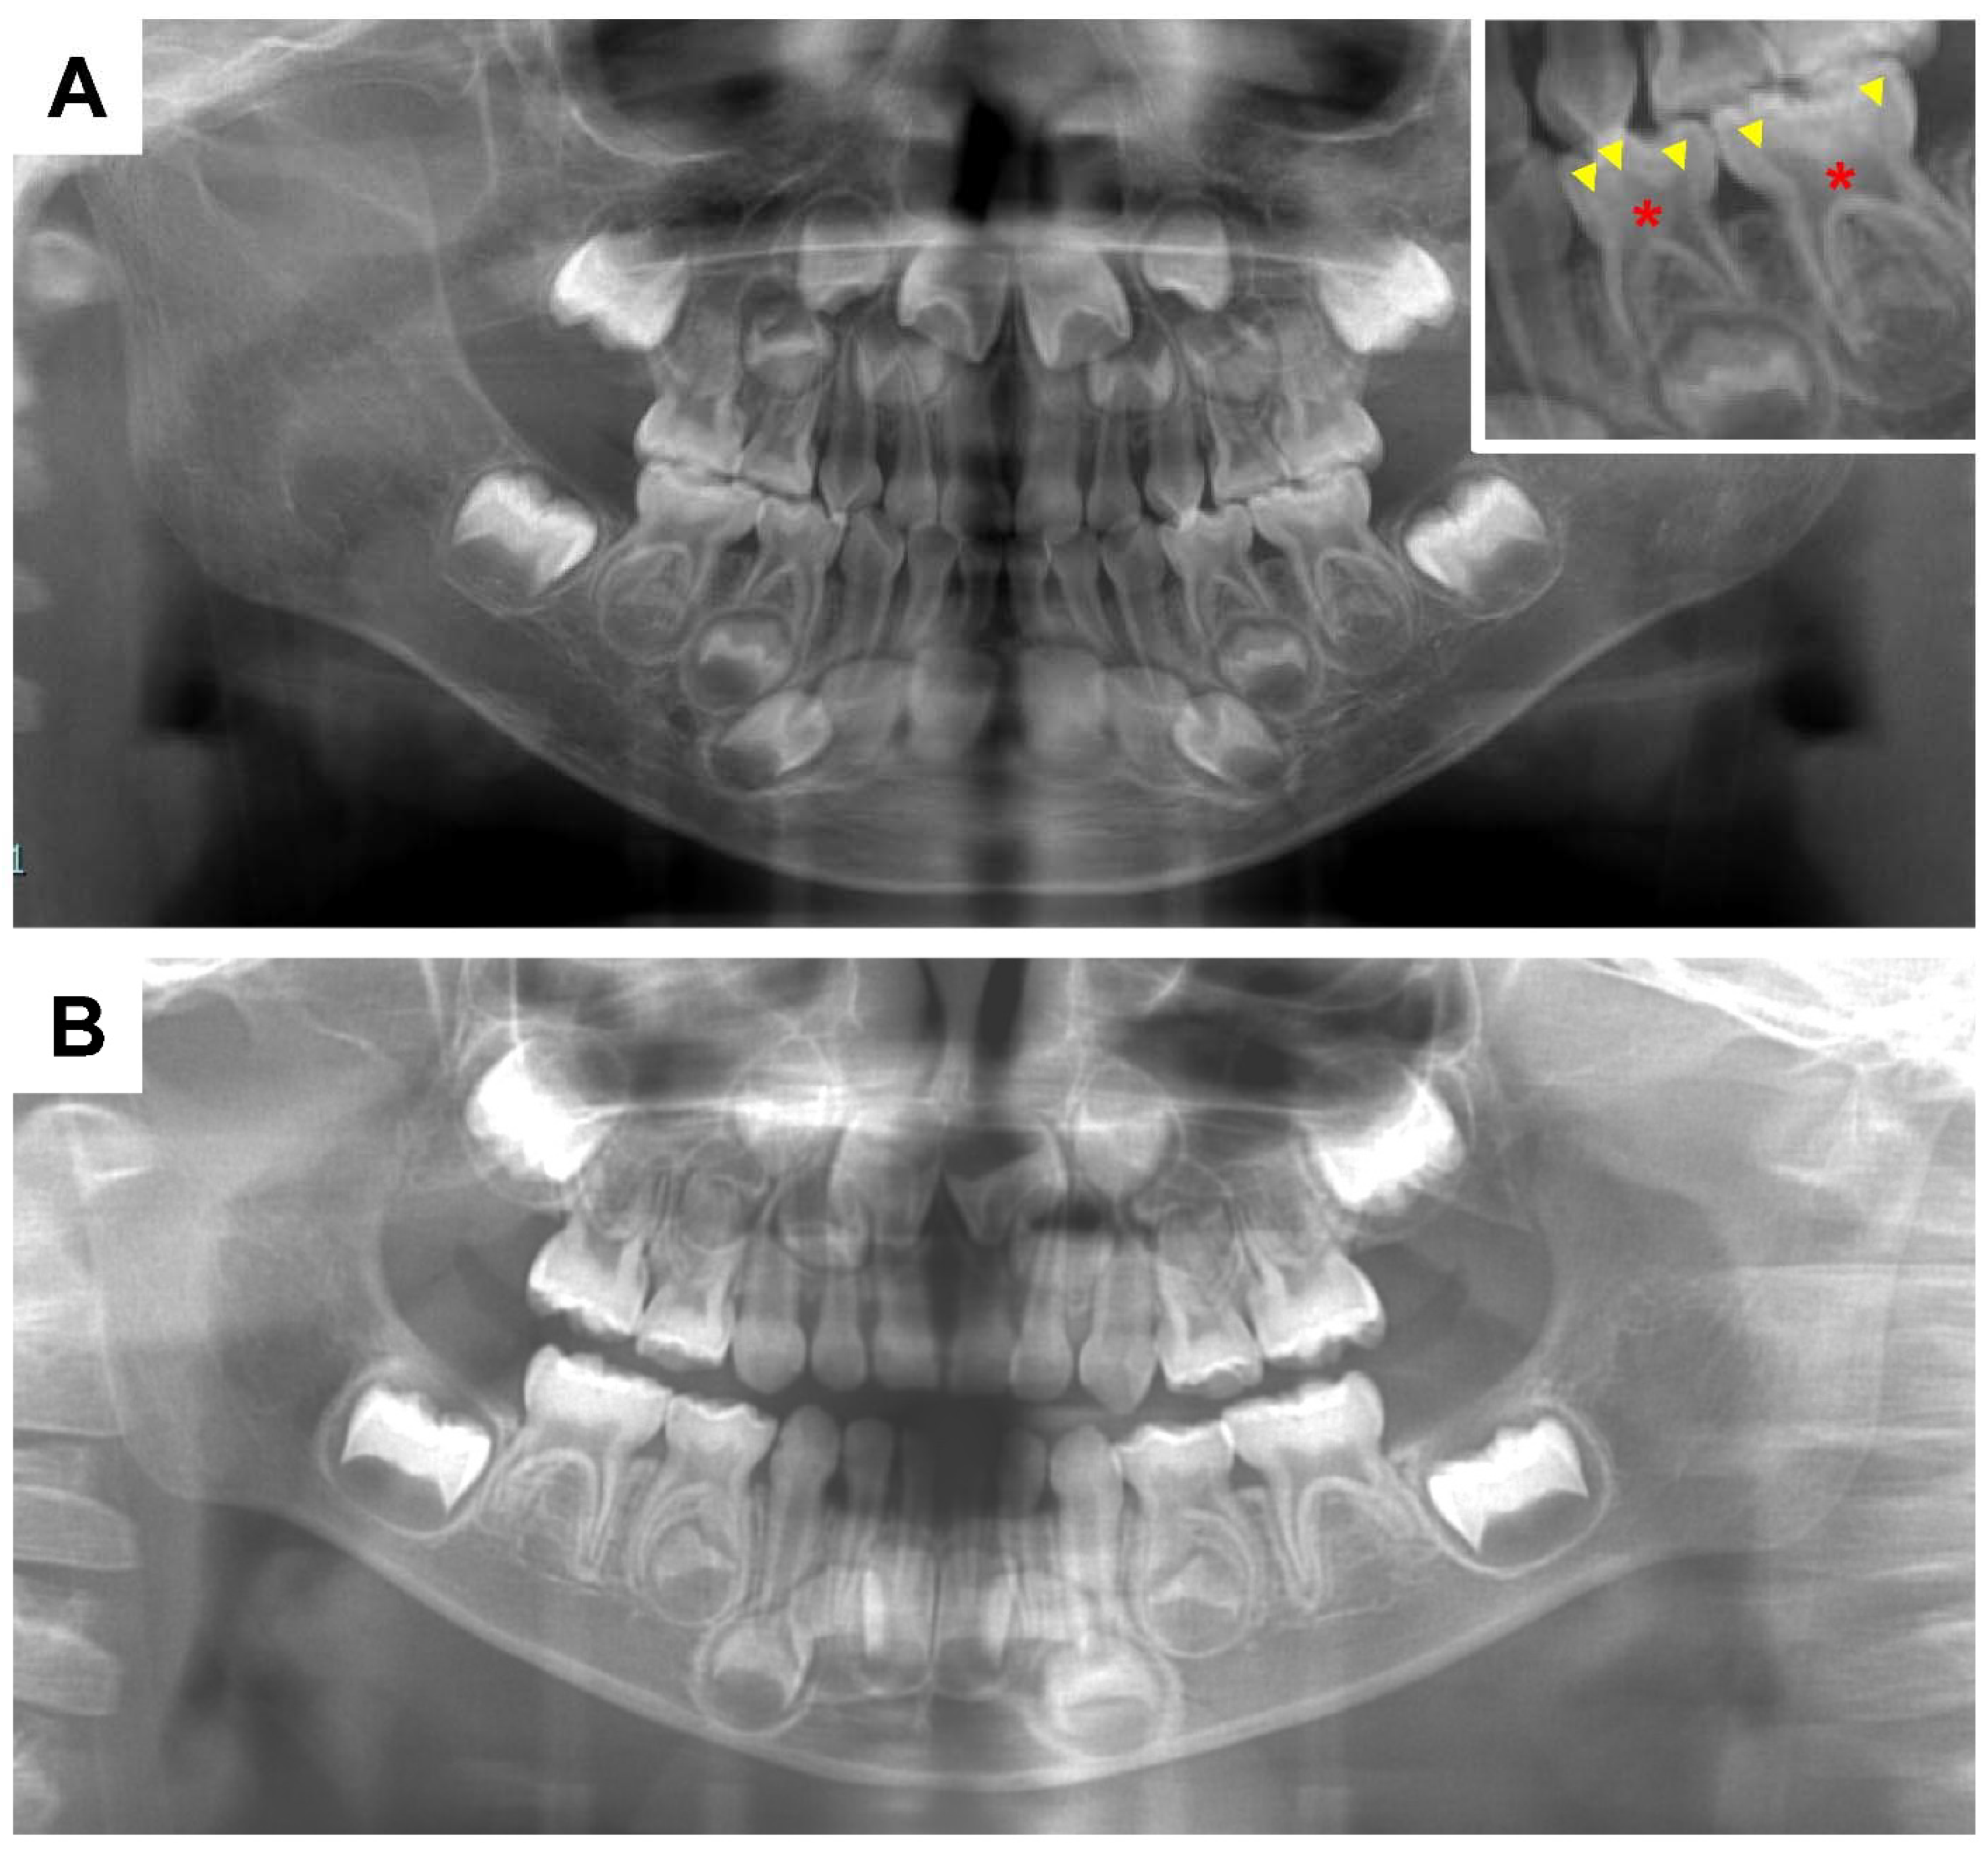

Figure 3.

Panoramic radiographs. (A) Female X-linked hypophosphatemia (XLH) patient aged 3 years 11 months. The square on the upper right is an enlargement of the primary mandibular left molar region. Wide pulp chambers (asterisks) and prominent pulp horns (arrowheads) can be seen. (B) Healthy age-matched female.